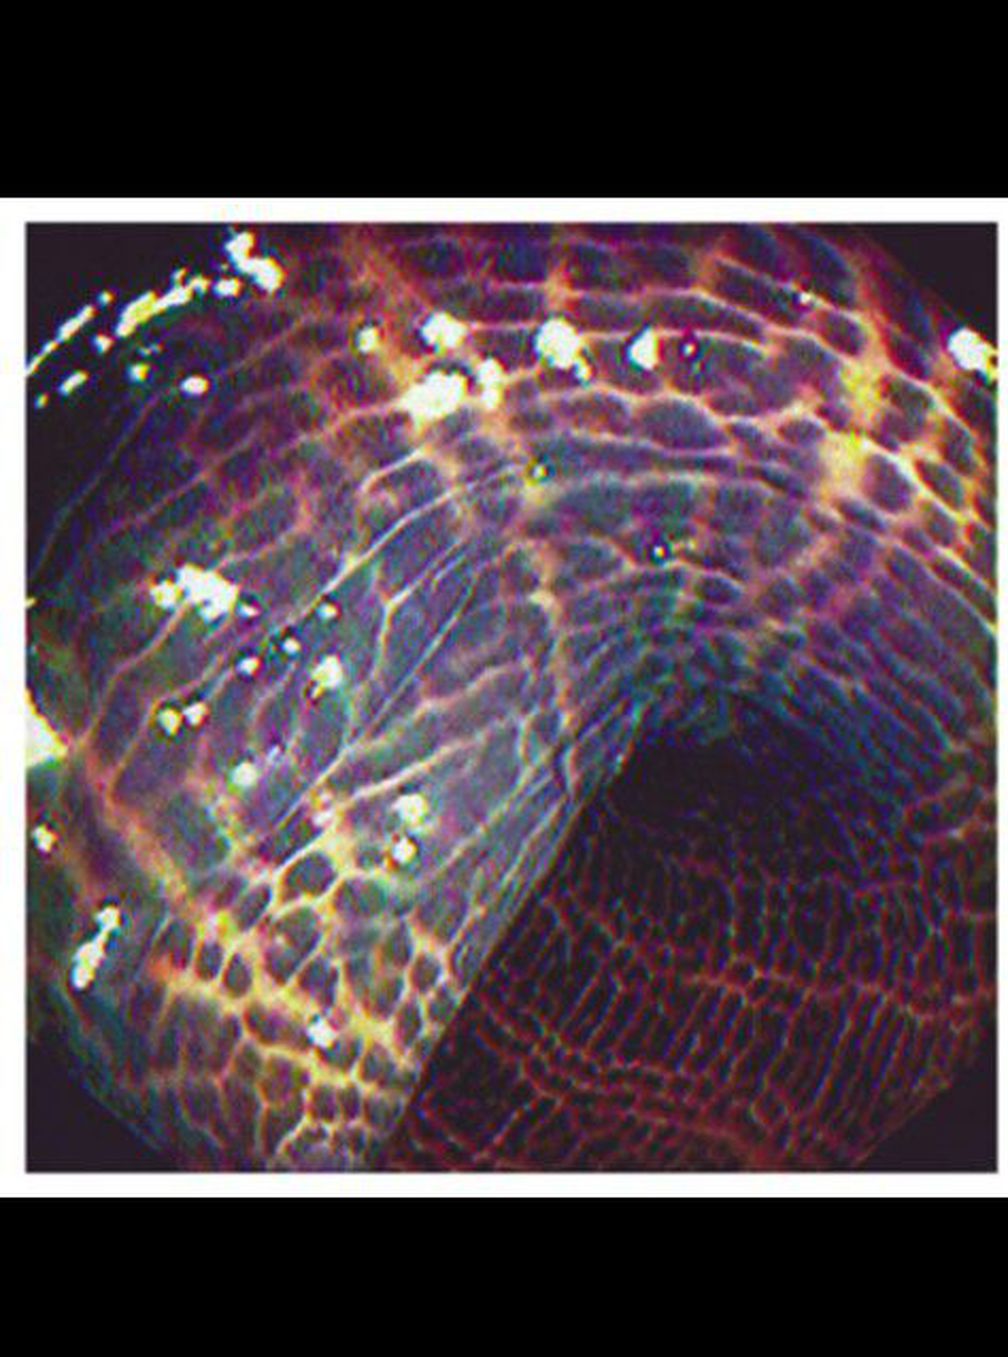

Melanosis coli is dark brown pigmentation of the colon that occurs with the use of laxatives containing anthraquinone, such as senna. It can develop within a few months of use, and it can disappear in a few months if the use of the laxative is discontinued.